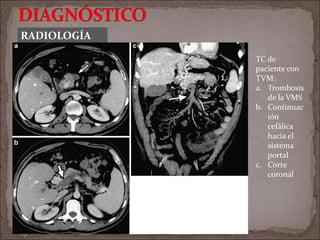

TC de

paciente con

TVM:

a. Trombosis

de la VMS

b. Continuac

ión

cefálica

hacia el

sistema

portal

c. Corte

coronal

RADIOLOGÍA